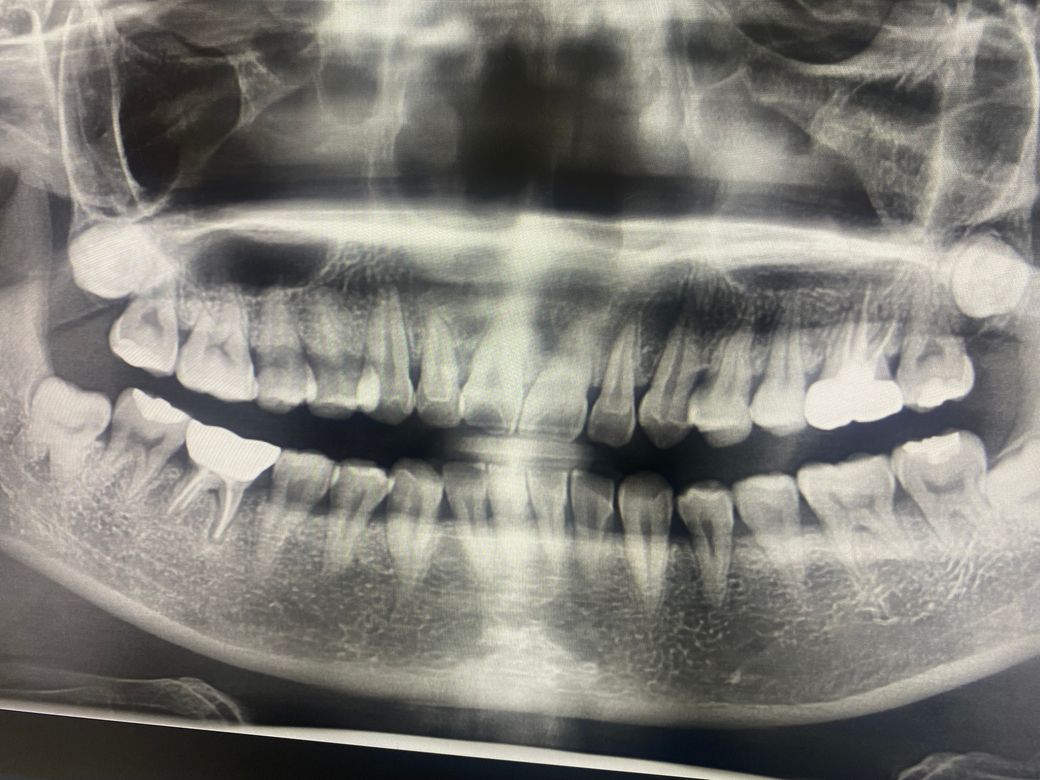

• 1번 째 사진

2. 다만 저 엑스레이상 상태를 보면 단순 잇몸만 문제가 있는것은 아니고 근관-치주의 복합적인 문제가 아닐까 싶습니다